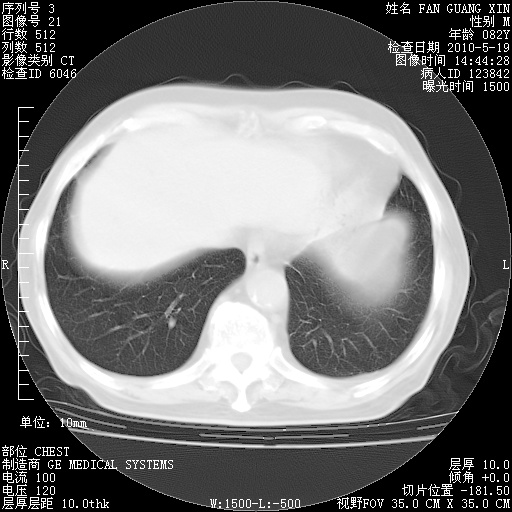

复查肺部CT,明显好转。为什么发热呢?

治疗3周后的肺部CT